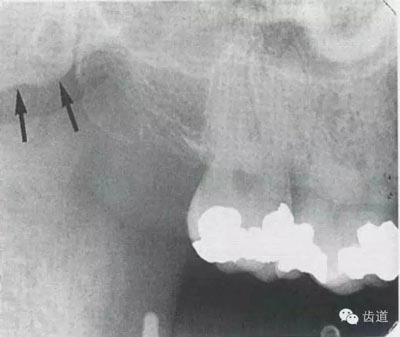

1)頦棘:

位于兩下中切牙根尖下方,下頜骨正中聯(lián)合處顯示為小圓形密度高的影像,在中心有點狀密度低的影像,其周圍骨小梁稀少,為骨松質(zhì)區(qū)。